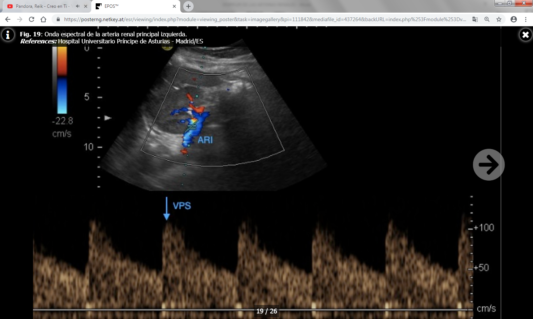

Los parámetros directos son más fiables y reproducibles que los indirectos, y son los siguientes:

- Velocidad picosistólica (VPS) : Normal por debajo de 180-200 cm/s.